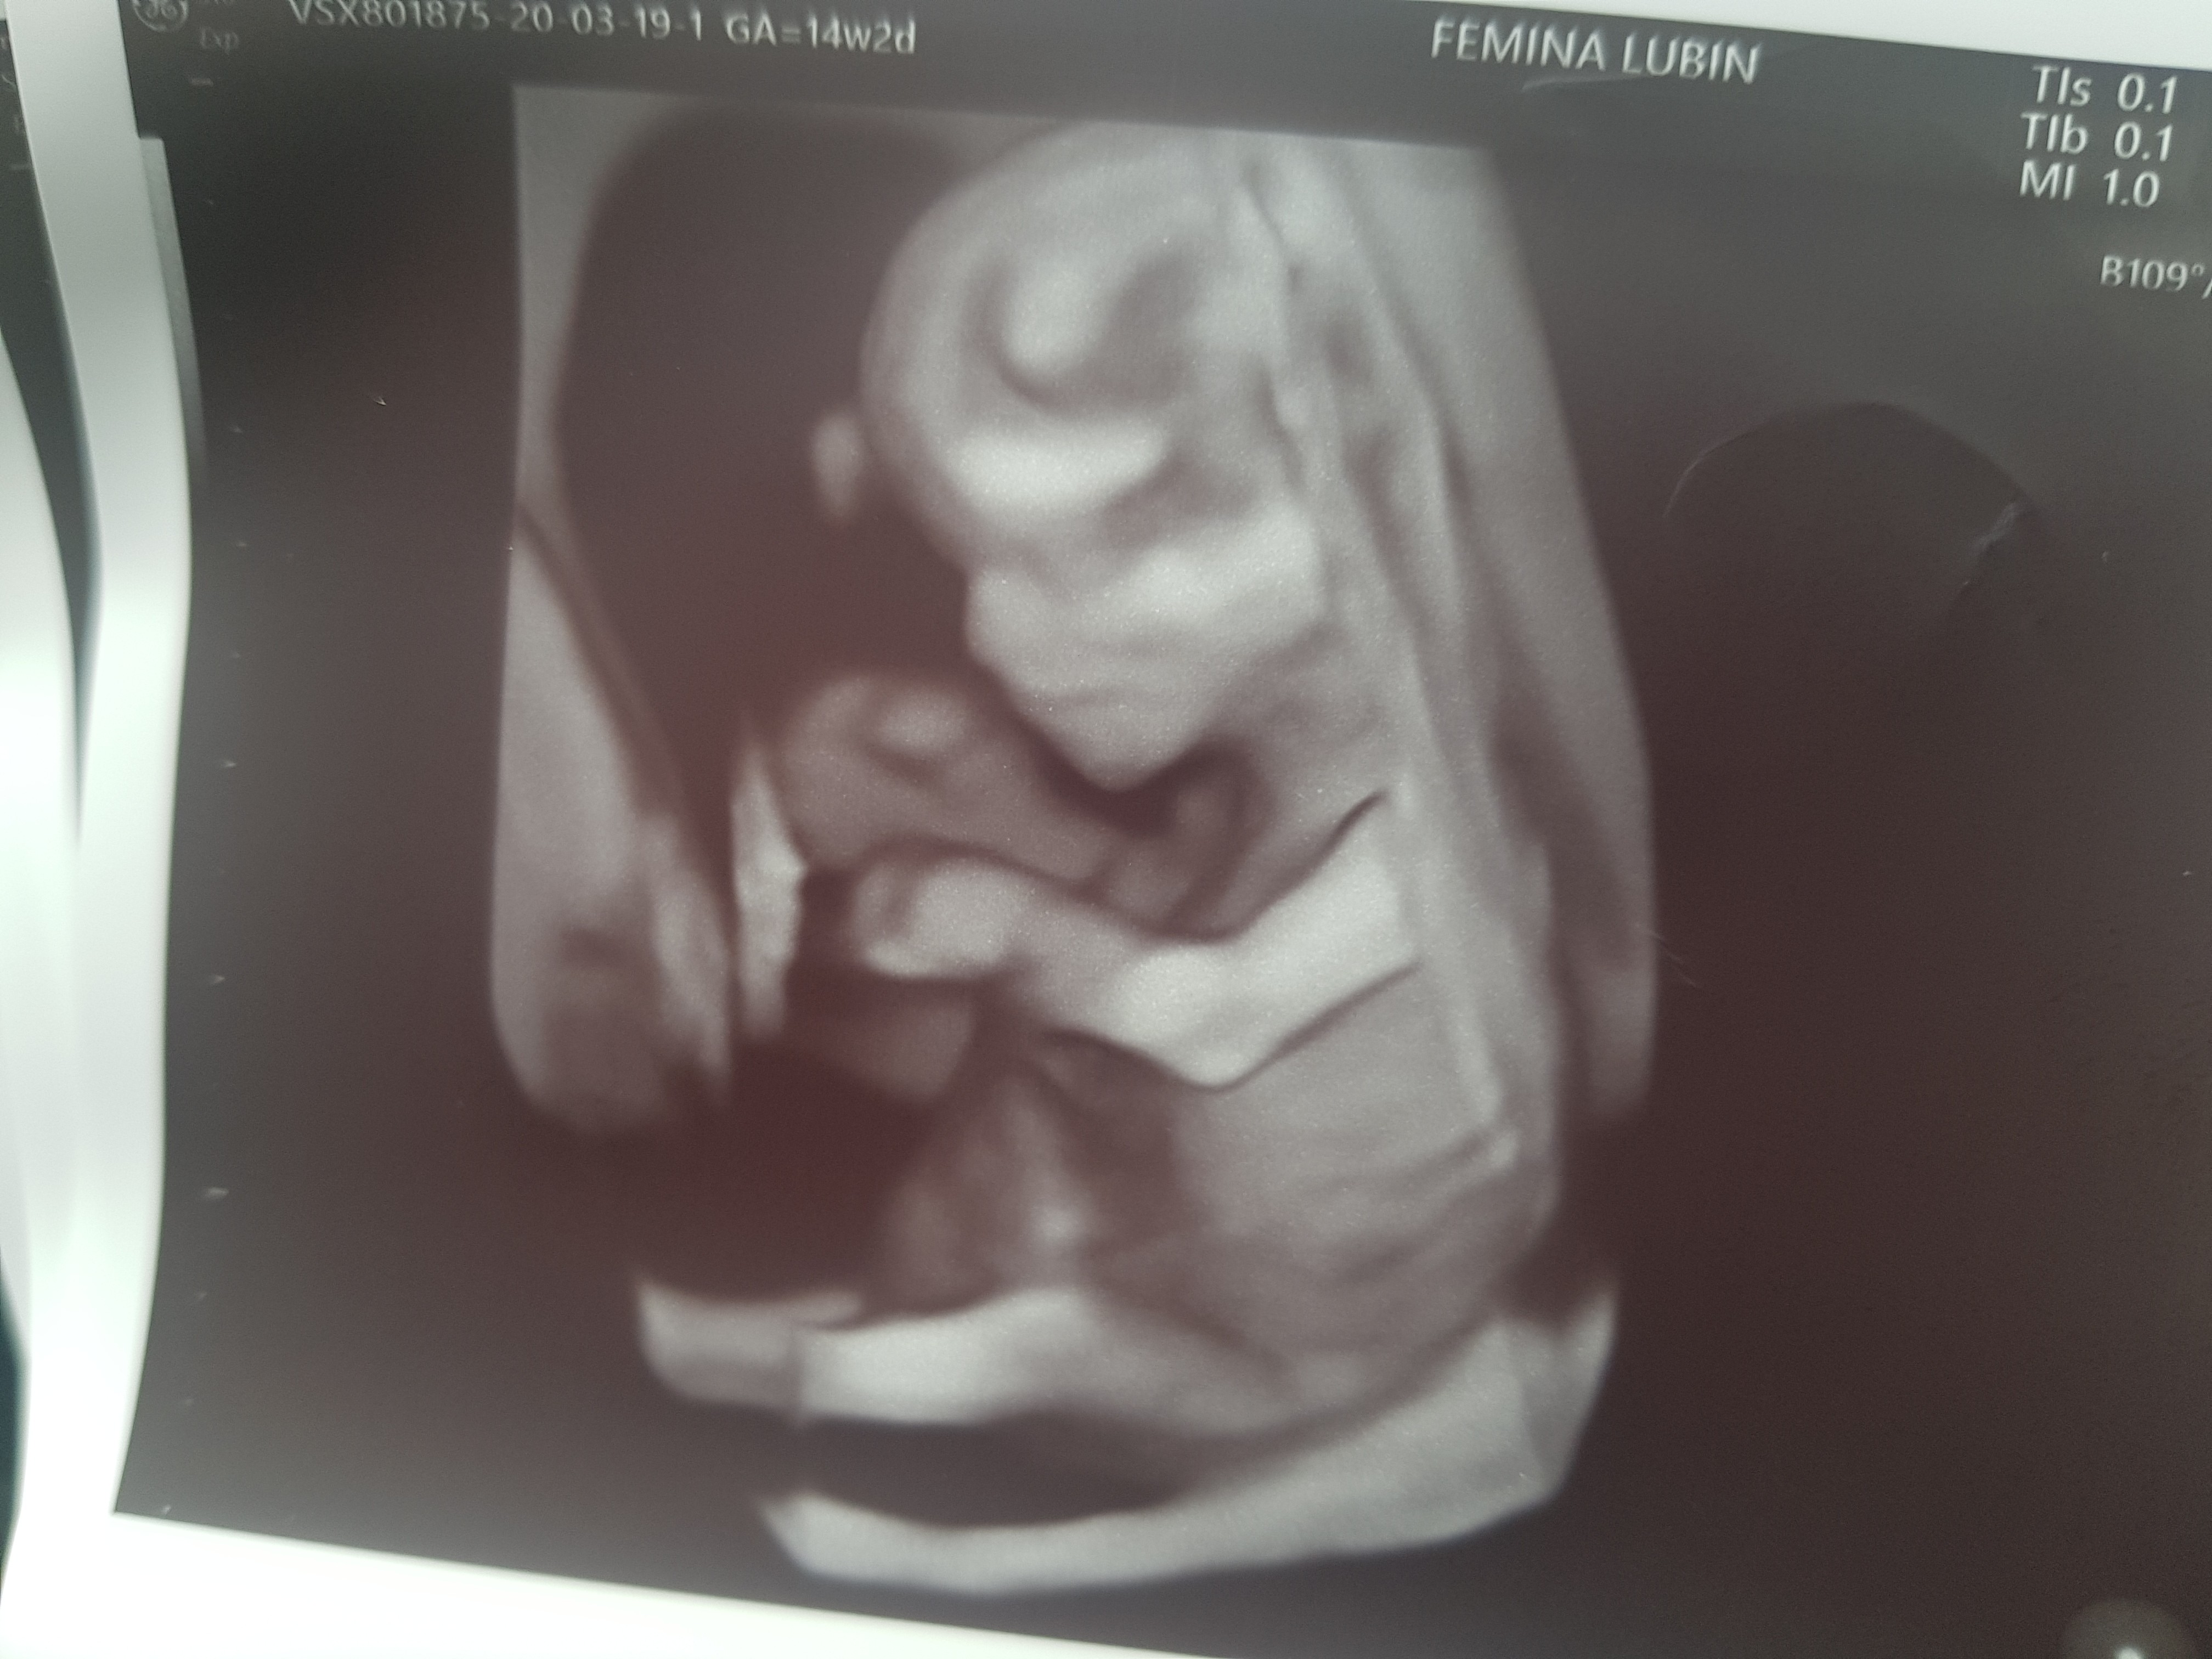

Właśnie wyszłam z prenatalnych, u dzidziusia wszystko dobrze, wszystko wg norm [emoji4][emoji16] i tak jak u dziewczyn termin przesunął mi się o kilka dni, prawdopodobnie będzie 29 września , 12 tc +1 dzien

A i na 70% będzie to dziewczynka [emoji16]

Udalo mi się też zapisać na połówkowe 14 maja :)Zobacz załącznik 1093818